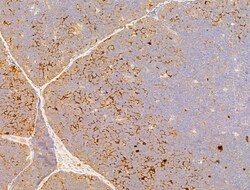

| Immunocytochemistry, Immunohistochemistry (Paraffin), Western Blot | |